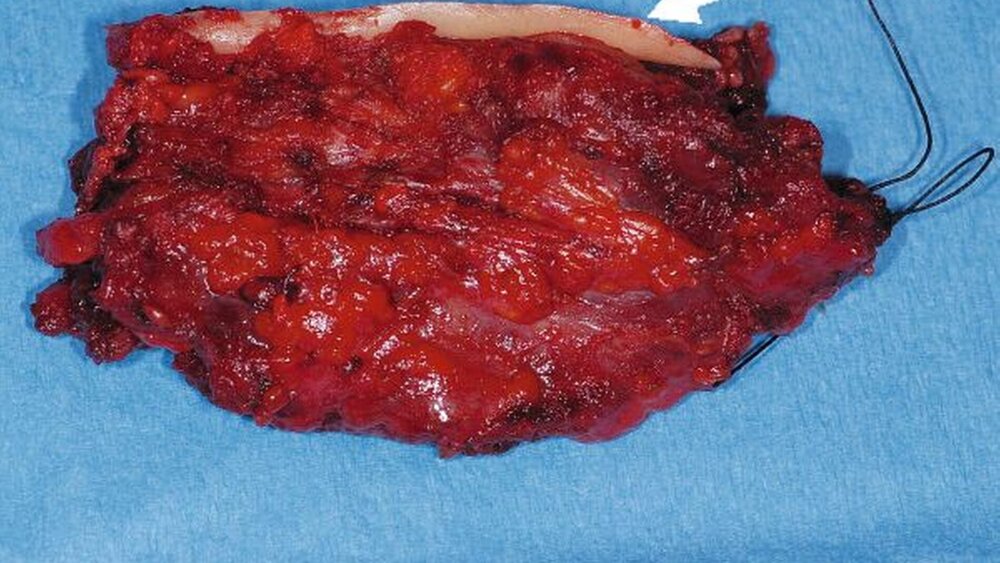

Die histopathologische Aufbereitung ergab schließlich ein Karzinom ex pleomorphem Adenom. Bei kleinherdigen Resten des pleomorphen Adenoms lagen Anteile eines insgesamt gering differenzierten, invasiven, duktalen Speicheldrüsenkarzinoms vor (Abbildungen 4 und 5). Aufgrund einer Infiltration in die angrenzende Skelettmuskulatur, einer angio-lymphatischen Karzinominvasion und einer Perineuralscheideninfiltration wurde in einem weiteren Eingriff nochmals nachreseziert. Es erfolgte die Resektion der basalen Anteile des Unterkiefers, des umliegenden Weichgewebes und die Entfernung der Lymphknoten der Level I bis V (Abbildung 6). Zur weiteren Therapie wurde mit dem Patienten die Durchführung einer adjuvanten Radiotherapie besprochen.